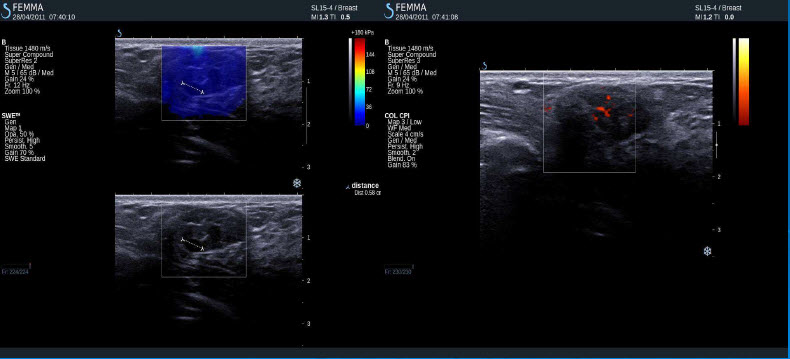

Pozitivní výsledky elastografie / histologicky potvrzená malignita

Invazivní duktální adenokarcinom

Inflamatorní karcinom

Invazivní lobulární karcinom

Invazivní duktální karcinom